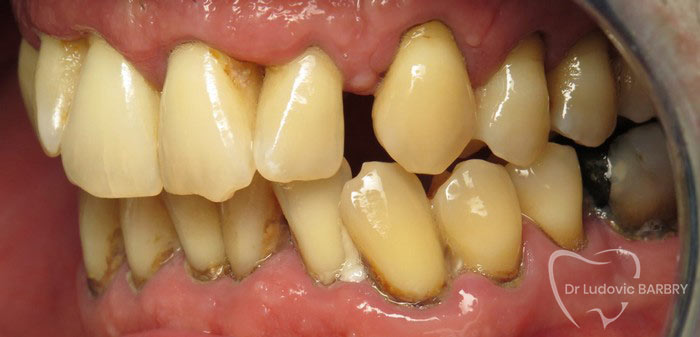

Parodontie Sévère

Grosse perte osseuse visible sur

la radio   on pourrait avec un stylet marquer en 2 couleurs le niveau osseux

actuel et normal

avant traitement